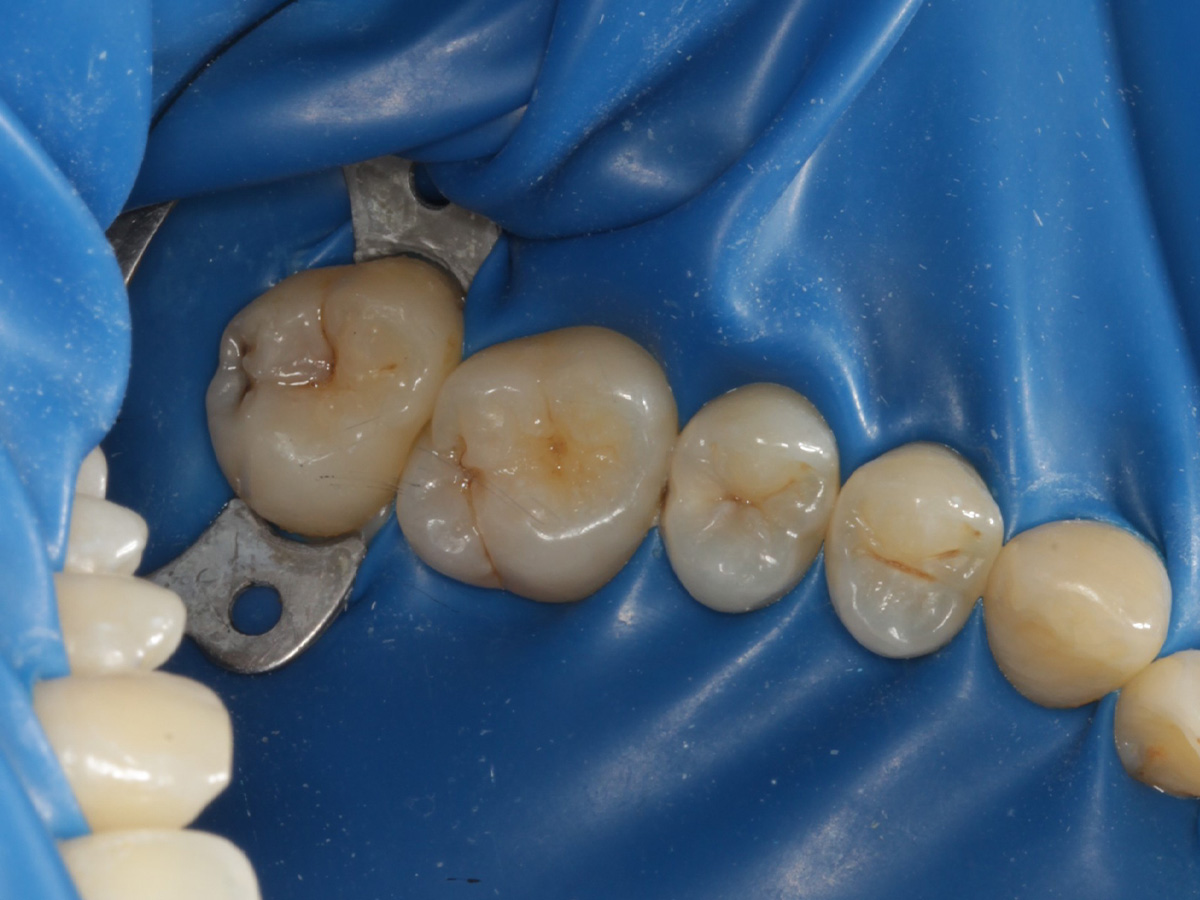

Behandlung einer tiefreichenden Karies an Zahn 25 distal

Tiefreichende kariöse Läsionen im distalen Bereich stellen häufig eine besondere Herausforderung dar, da sie sowohl eine präzise Kavitätenpräparation als auch eine anspruchsvolle Rekonstruktion der Kontaktpunkte erfordern. Durch Anwendung der Bioclear Evolve Matrizen konnten in diesem Fall eine ästhetisch und funktionell hochwertige Versorgung erzielt werden, die gleichzeitig minimalinvasiv und substanzschonend war.

Abbildung 1

Approximalraumkaries an Zahn 25 distal